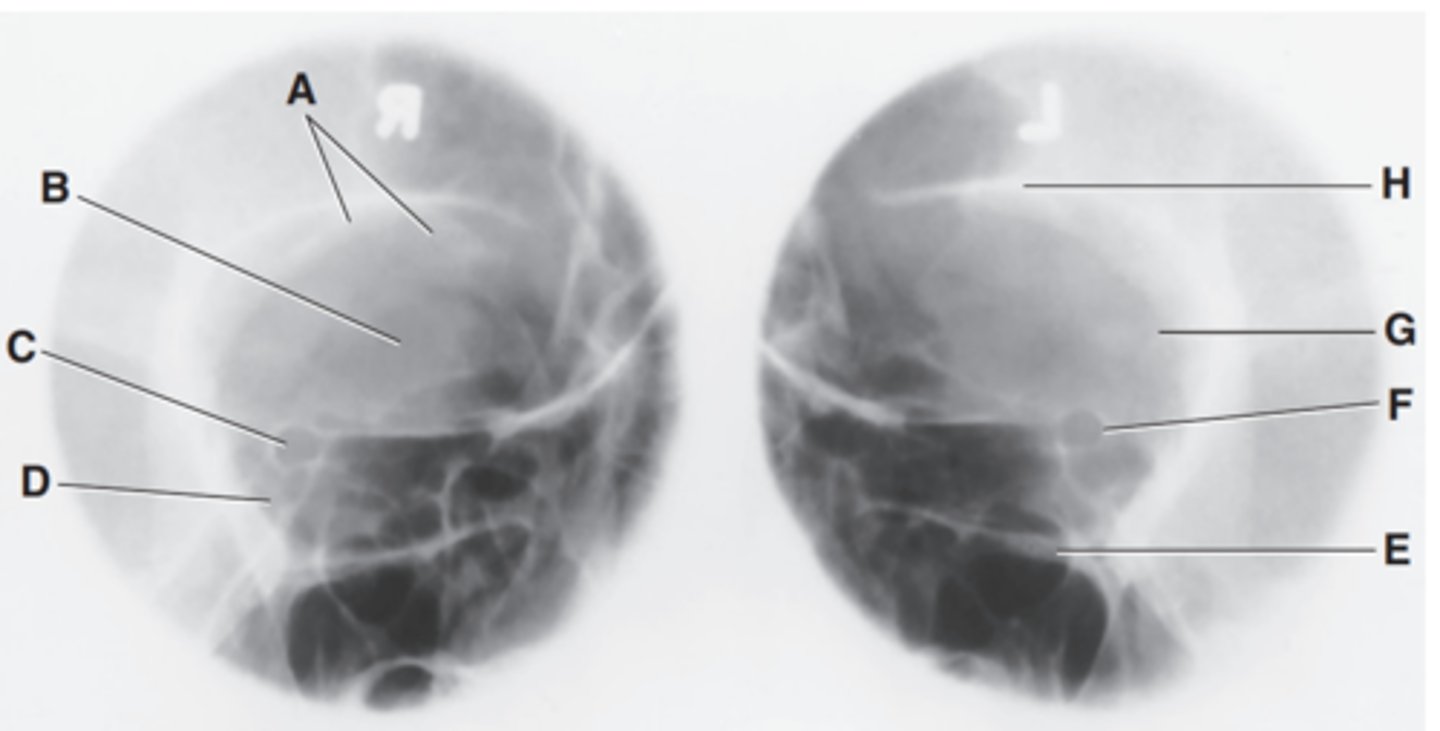

Label A

Posterior clinoid processes

Label B

Petrous ridge or petrous pyramid

Label C

Parietal bone

Label D

Occipital bone

Label E

Foramen magnum

Label F